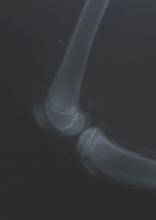

De diagnose is te stellen door een dierenarts die de op de hoogte is van de bouw van een kniegewricht. De patella is met duim en wijsvinger vast te pakken en zo kan er worden nagegaan of er een abnormale beweeglijkheid aanwezig is. Mogelijk kan ook een stationaire patellaluxatie worden vastgesteld.

Met behulp van röntgenfoto's is ook de oorzaak van de patellaluxatie vast te stellen.

Zo kunnen diepte van de groeve, de hoek van het kniegewricht en de belijning van het dijbeen zichtbaar worden gemaakt en worden gemeten. In het dierenziekenhuis te Dordrecht worden deze metingen altijd voor de operatie verricht om de operatietechnieken er op aan te kunnen passen.

De sleuf in het bovenbeen is hier te beoordelen. |